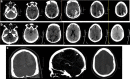

Findings: This is a case study report; with review of previously published literature through PubMed search. We describe the case of a 25 year old man following bariatric surgery who increased his ingestion of ondansetron, taking up to 40 tablets/day due to excessive nausea and vomiting. The patient was hospitalized for progressively more severe headache of 1 week's duration. Computed tomography (CT) revealed bilateral cerebral edema in the parietal and occipital lobes in the setting of elevated blood pressure (BP). Three days into his admission, following improvement in his BP with oral anti-hypertensive but continued use of the ondansetron, the patient developed near complete blindness. CT head imaging revealed progression of the posterior cerebral edema and intraparenchymal hemorrhage. He was admitted to our ICU and despite supportive treatment, his neurological examination worsened while CT head imaging findings remained stable. Invasive multimodality monitoring revealed elevated intracranial pressure. The patient was aggressively treated and after a prolonged hospitalization and rehabilitation course, made a significant recovery.